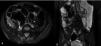

A previously healthy 48-year-old man came to the emergency service presenting with diffuse abdominal pain of three-month progression, associated with periods of diarrhea, bloating, and weight loss of approximately 10kg. Upon admission, his vital signs were within normal parameters and abdominal examination showed no peritoneal irritation, masses, or visceromegaly. A calprotectin stool test reported fecal calprotectin of 2,351μg/g (reference value:<50μg/g) and a lower gastrointestinal barium x-ray revealed filiform contrast medium passage at the level of the ileum (string sign) (Fig. 1). During colonoscopy, active ulcerative ileitis was observed, with a polyp at the mouth of the ileocecal valve. The anatomopathologic study reported mild diffuse chronic inflammation (Fig. 2). Given the diagnostically inconclusive results, magnetic resonance enterography was performed, and the findings were consistent with Crohn’s disease (CD) (Fig. 3 A and B). Treatment for moderate ileal CD was indicated: induction therapy with oral steroids and the later addition of thiopurines for remission maintenance. At three months of follow-up, the patient experienced symptom improvement, weight gain, and the absence of flare-ups.

Magnetic resonance enterography, BTFE sequence: A) axial view, B) coronal view. Severe thickening and parietal stratified-looking edema of the terminal ileum (arrow heads) with thickness up to 20mm and length of 10cm, conditioning luminal narrowing (arrow) with 98% stricture, associated with edema of the mesenteric fat. The MaRIA scoring system was employed, adding the individual scores of the six segments (rectum, sigmoid colon, descending colon, transverse colon, ascending colon, and ileum), obtaining a global index of 3 points.